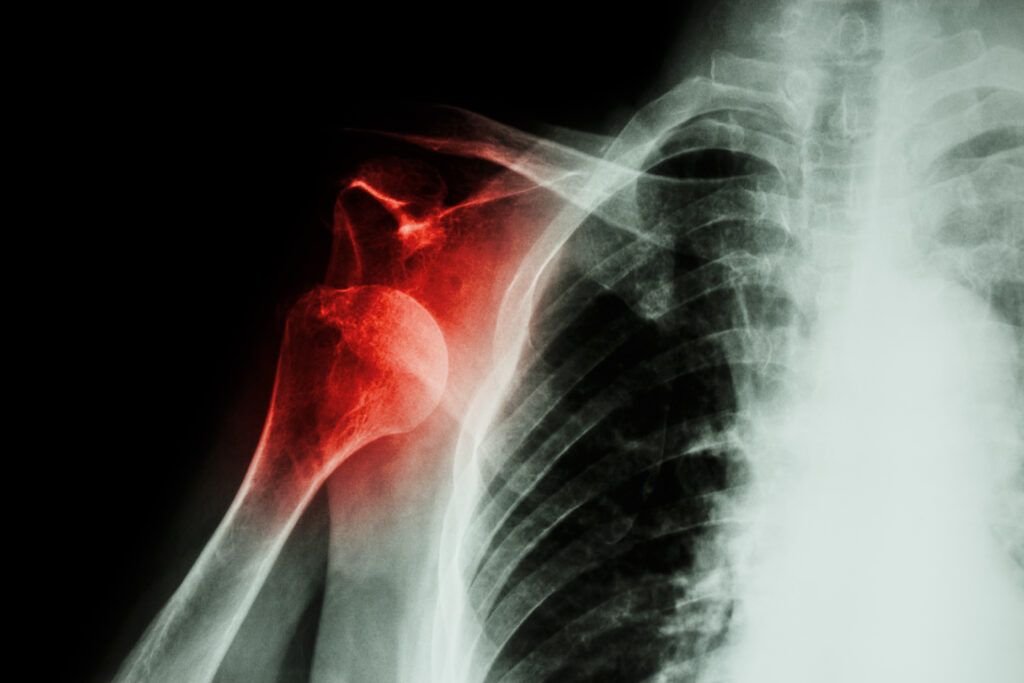

Luxația umărului

Luxația de umăr reprezintă pierderea contactului dintre suprafețele articulare, de obicei ca urmare a unui traumatism.

La primele episoade de luxație, structurile care asigură stabilitatea umărului – capsula articulară,labrumul, ligamentele și uneori marginea osoasă a glenei omoplatului – se pot rupe. În aceste condiții, umărul rămâne instabil, se luxează “sare” din ce în ce mai ușor, afectează viața de zi cu zi și se deteriorează progresiv cu fiecare nou episod. În astfel de cazuri, este necesară o stabilizare chirurgicală.